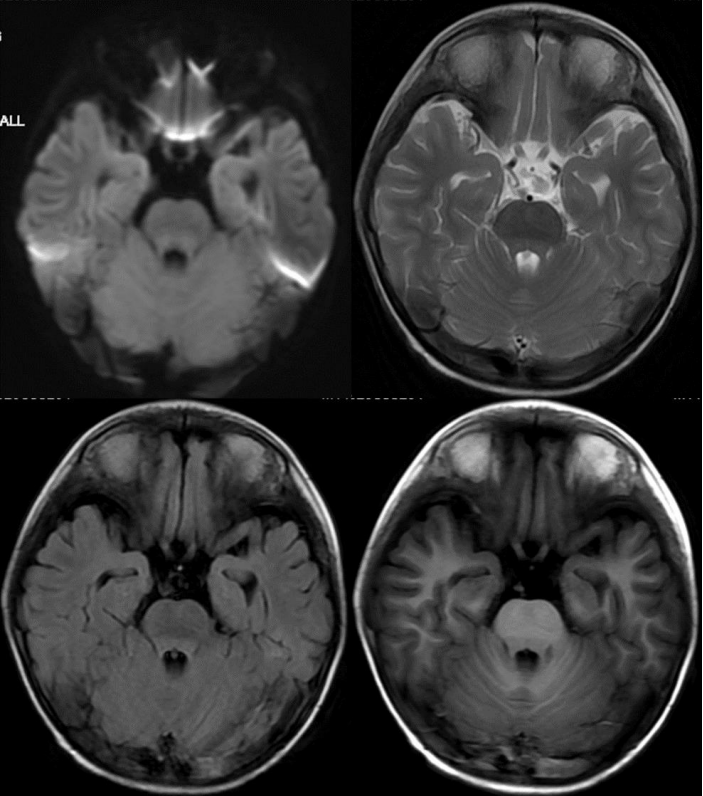

MUSE DWI 1000,168 × 264,提示双侧额叶皮层弥散受限。

除此之外,海马的信号怪怪的,是什么?所以,我们加扫海马矢状位小视野弥散。

•Sag FOCUS DWI 1000,FOV = 22 × 8.8cm,2.0 / 0.0 mm

海马最外层呈弥散受限表现,但是总感觉雾里看花,并不清晰。我们还能做什么?